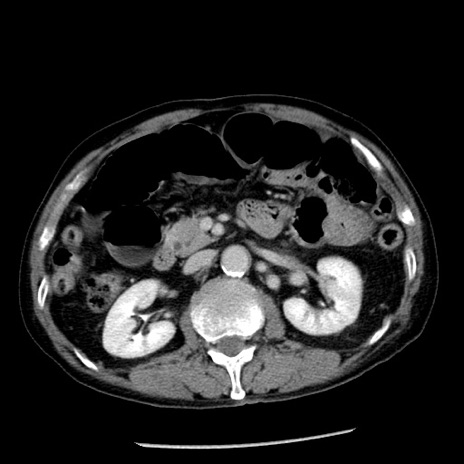

症例26(横断像)

【症例】80歳代男性

【主訴】嘔吐

【現病歴】昨晩2回嘔吐あり、今朝になっても嘔吐あり。来院。

【既往歴】胃潰瘍

【身体所見】意識清明、BT 37.6℃、BP 166/95mmHg、HR 100bpm、SpO2 97%、腹部:平坦・軟、腸蠕動音聴取良好、圧痛なし。

【データ】WBC 21900、CRP 1.46